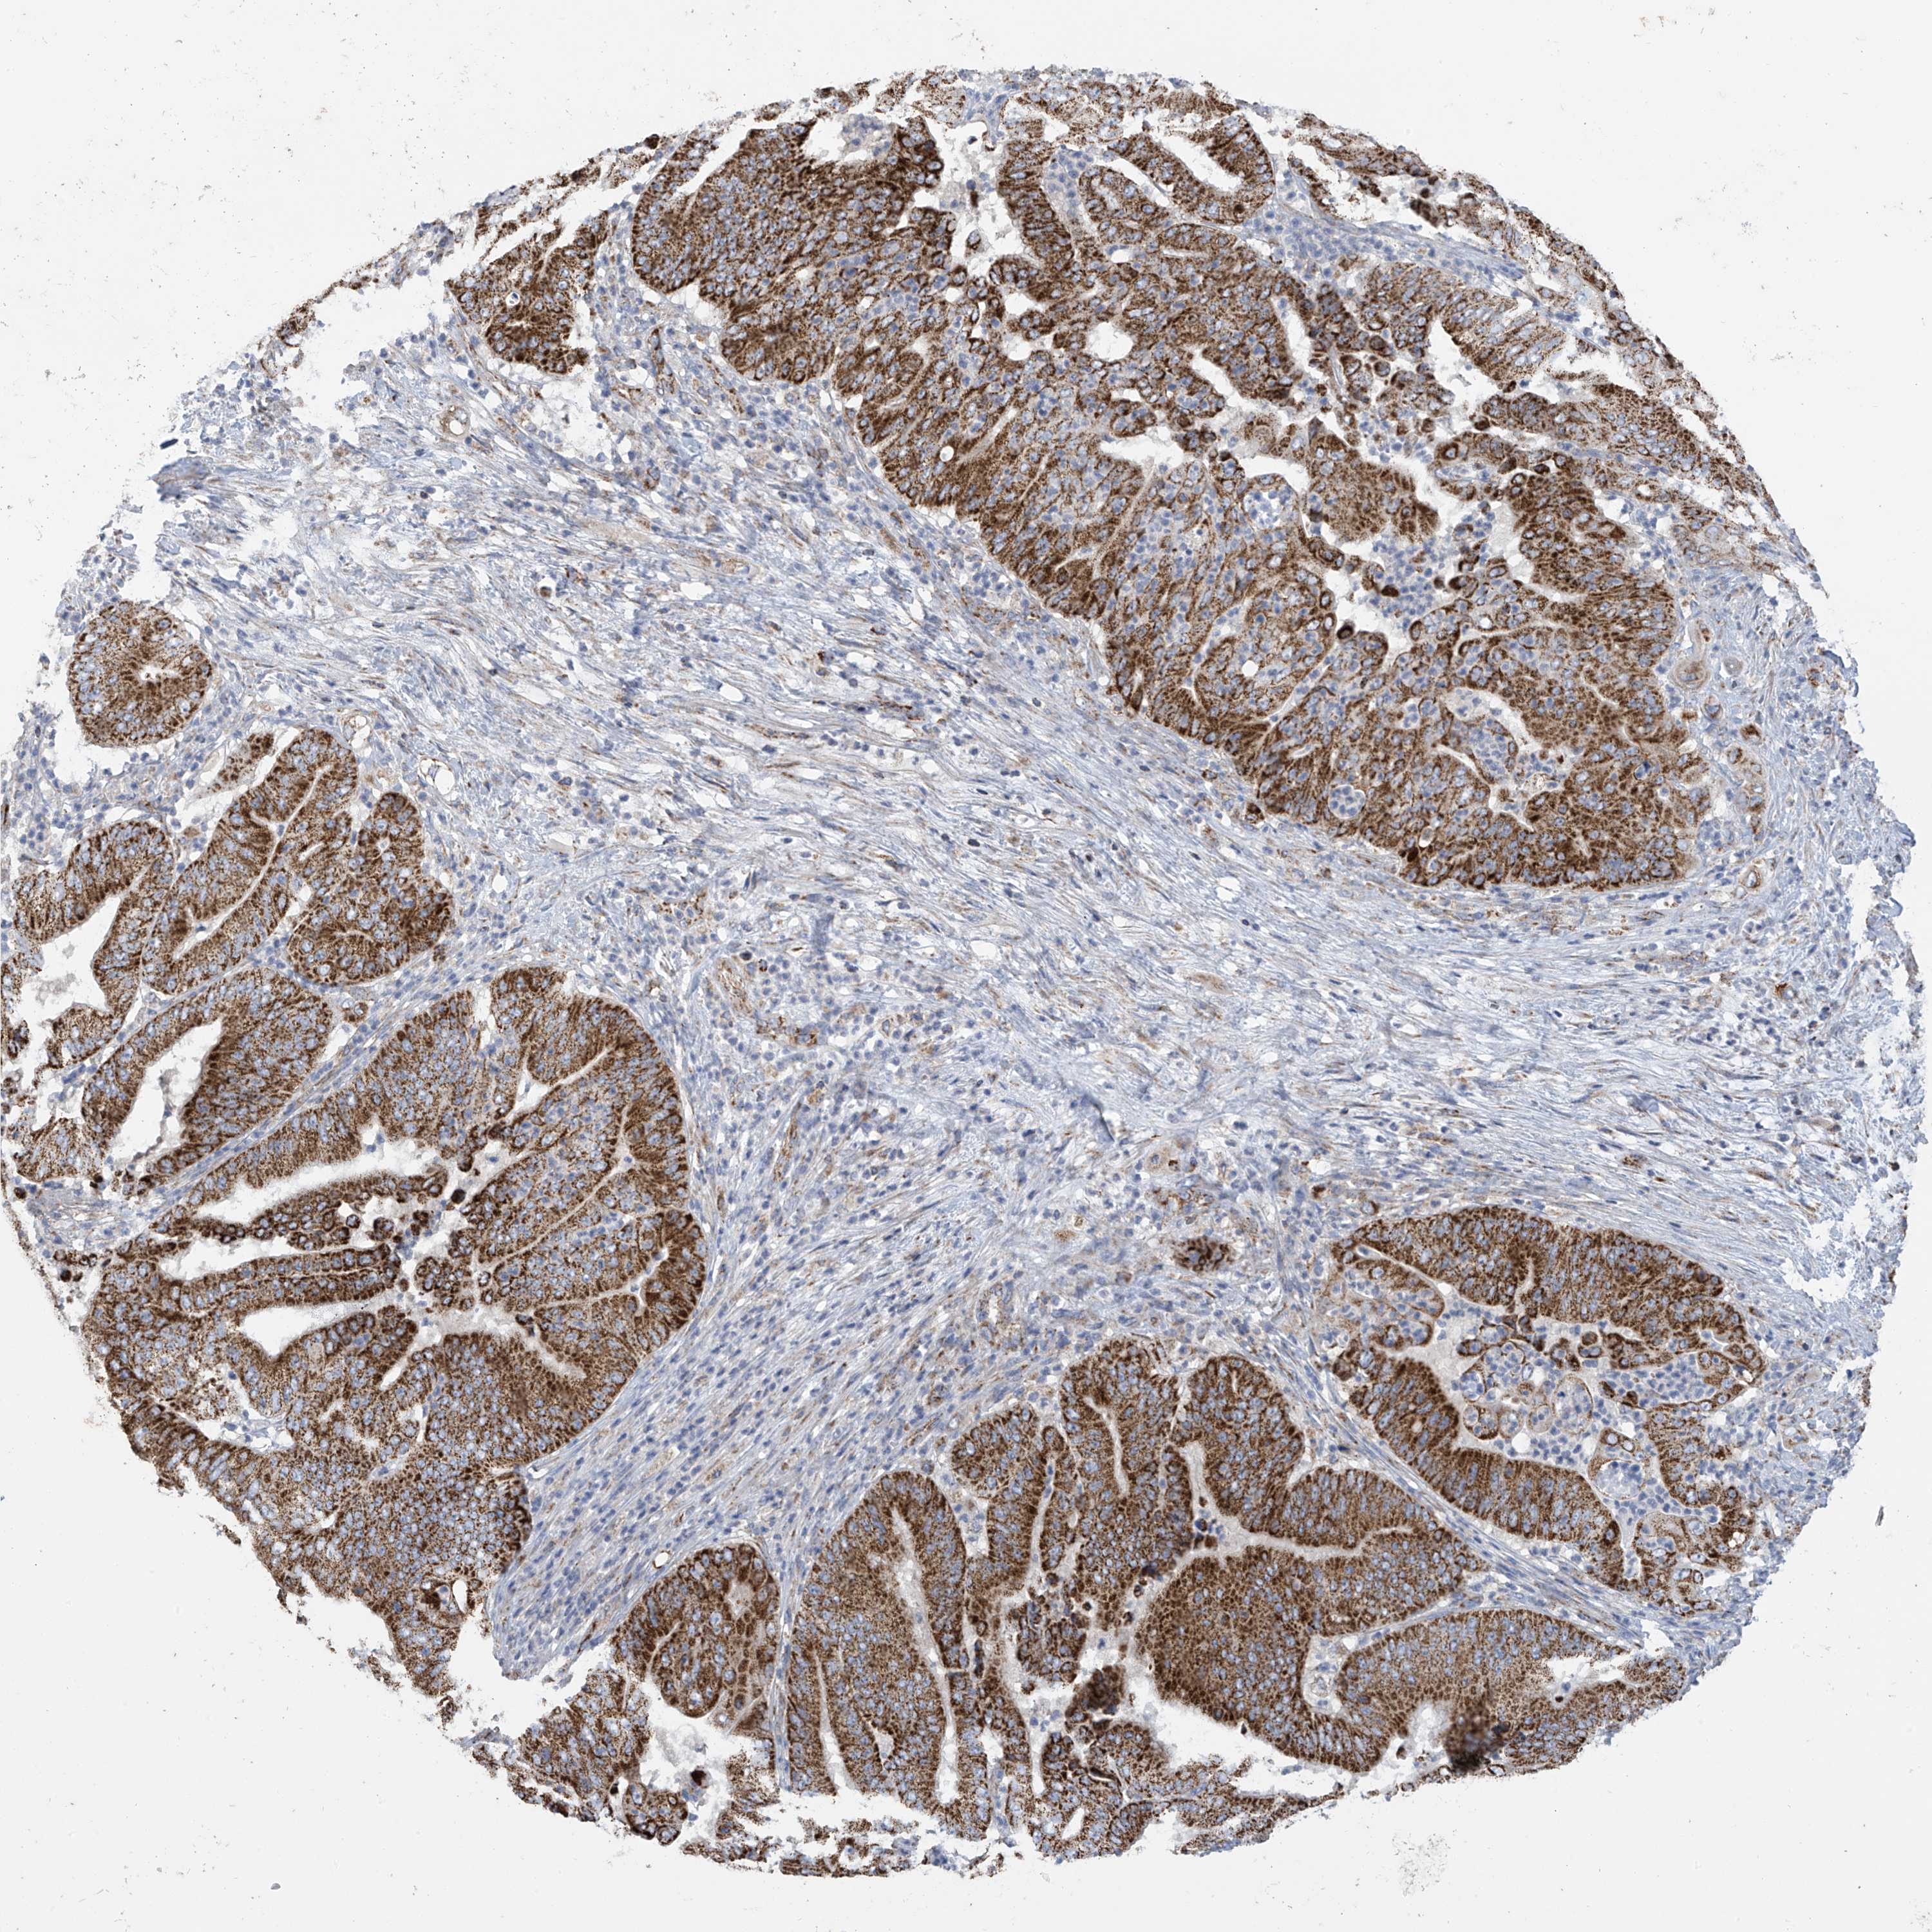

PANCREATIC CANCER - Protein expressioni

A mouse-over function shows sample information and annotation data. Click on an image to view it in a full screen mode. Samples can be filtered based on level of antibody staining by selecting one or several of the following categories: high, medium, low and not detected. The assay and annotation is described here.

Note that samples used for immunohistochemistry by the Human Protein Atlas do not correspond to samples in the TCGA dataset.

Antibody stainingi

Antibody staining in the annotated cell types in the current human tissue is reported as not detected, low, medium, or high, based on conventional immunohistochemistry profiling in selected tissues. This score is based on the combination of the staining intensity and fraction of stained cells.

Each image is clickable and will lead to virtual microscopy that enables deeper exploration of all samples and also displays staining intensity scores, fraction scores and subcellular localization as well as patient and tissue information for each sample.

Antibody HPA034602

Antibody HPA034603

Antibody CAB033424

Staining

High

Medium

Low

Not detected

Intensity

Strong

Moderate

Weak

Negative

Quantity

>75%

75%-25%

<25%

None

Location

Nuclear

Cytoplasmic/membranous

Cytoplasmic/membranous,nuclear

Adenocarcinoma, NOS